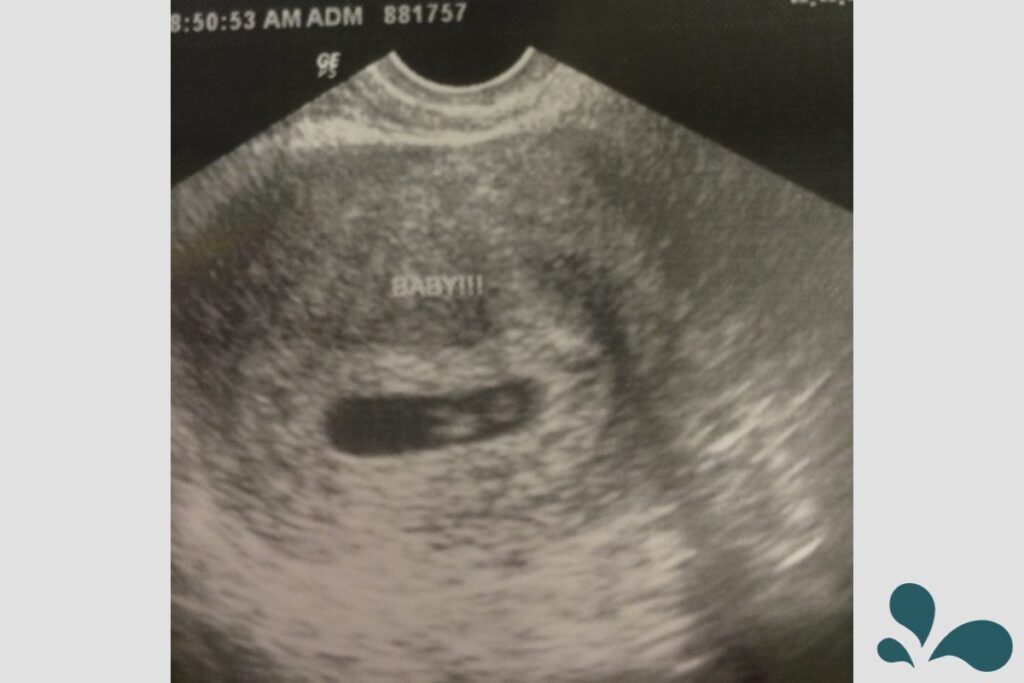

On April 25, 2016, exactly 2 years ago today, we had our first ultrasound and we got to see our unborn baby for the first time. It was incredible. It finally felt real. I had a living thing inside of me. We got to see and hear the baby’s heartbeat. I was in love.

The rest of the pregnancy and delivery went well. I will share my birth story later. My daughter has 2 cousins that are her same age; 3.5 and 2 months older. It’s wonderful.